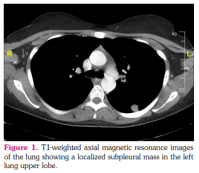

A 25-year-old female patient was admitted to our hospital for the tests requested during the job application. She had no complaints and no known systemic disease. Computed tomography revealed a localized subpleural mass in the left lung upper lobe (Figure 1). Positron emission tomography was performed to assess the spread, as malignancy was suspected clinically. The mass was 1.5 cm in diameter and increased 18F-fluorodeoxyglucose uptake with a maximum standardized uptake value of 3. Lung wedge resection was performed for diagnostic purposes. A gray-yellow colored, relatively well-circumscribed lesion was observed on the lung wedge resection material (Figure 2). Microscopic examination revealed a nodular lesion in the lung parenchyma characterized by intense lymphoplasmacytic infiltration, lymphoid follicles, and fibrosis. In immunohistochemical studies, approximately 150 to 200 plasma cells showed positive staining with the IgG4 antibody in a high-power field (HPF) (Figure 3). The ratio of IgG4/immunoglobulin G (IgG)-positive plasma cells was over 50%. When the patient's serum immunoglobulin levels were analyzed after the operation, the level of serum IgG4 was found to be 141 mg/dL (range, 0 to 125 mg/dL). As a result of clinical, laboratory, morphological, and immunohistochemical staining, the patient was found to be compatible with IgG4-RD. The patient was followed postoperatively and no additional treatment was given.

Furthermore, IgG4-RD may occur radiologically as hilar or mediastinal lymphadenopathy, bronchovascular bundle thickening, nodules, pleural involvement, ground-glass opacity, and alveolar interstitial involvement.[4] It is most commonly seen as lymphadenopathy and solitary nodule, respectively. When encountered as a nodule, lung cancer should be considered in the differential diagnosis.[1] In our case, the lesion was radiologically in the form of a solid nodule which suggested a suspicion of malignancy.